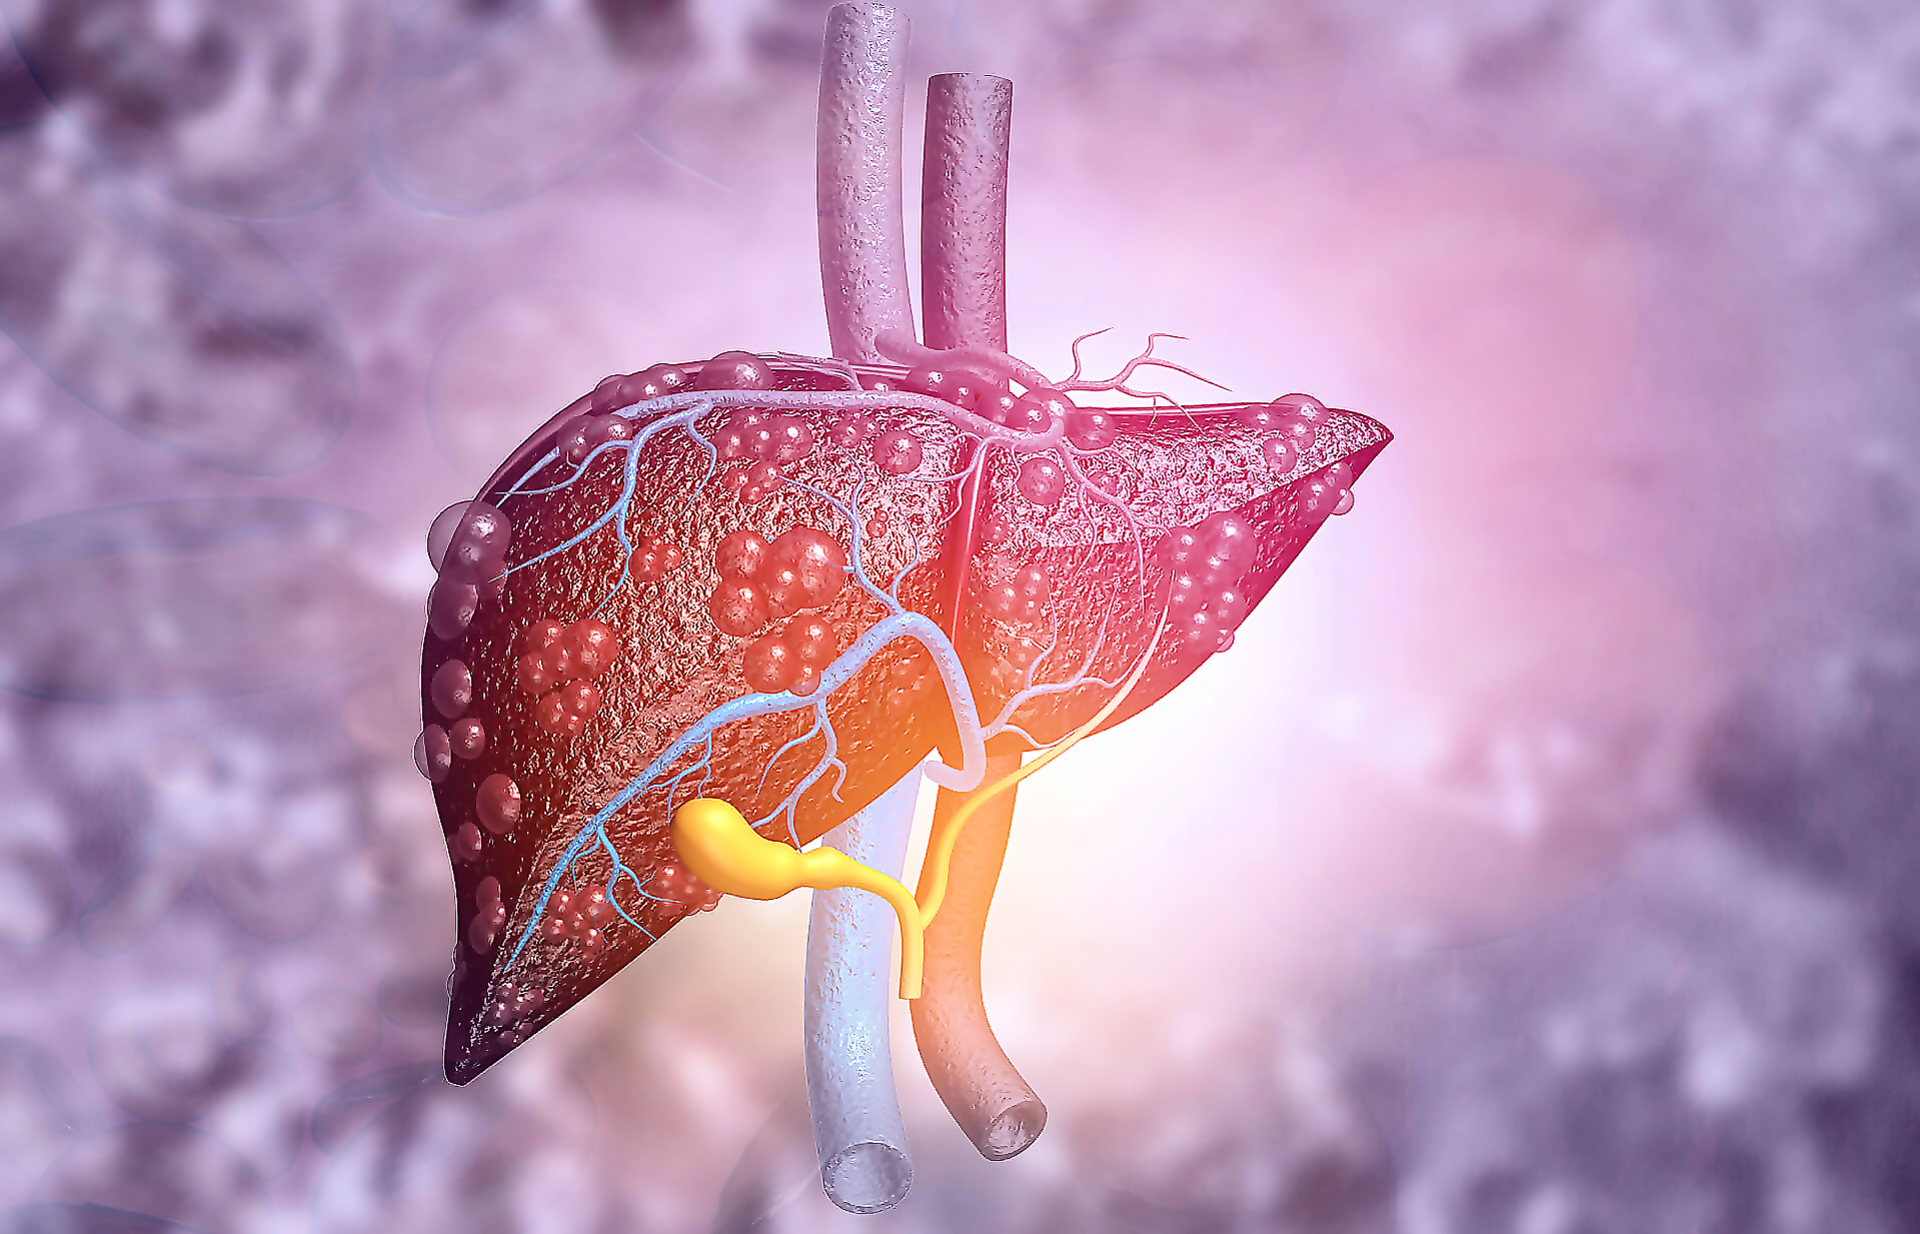

Изображения заболеваний печени: признаки и симптомы